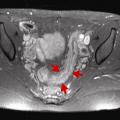

Bartholinite aiguë

MALADIES DE LA VULVE